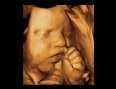

4D ultrazvuk predstavlja najsavremeniji način pregleda trudnica, gde se ultrazvučni talasi softverskim putem  pretvaraju u sliku fetusa, koja je izuzetno jasna i fascinantna roditeljima koji sve vreme mogu da posmatraju svoju još nerođenu bebu. Na ovaj način veza između roditelja i bebe postaje još jača.

4D ultrazvuk ima i četvrtu dimenziju-vreme i na taj način se dobija prikaz pokreta fetusa u realnom vremenu. Kada je u pitanju kasnija faza trudnoće, mogu se, pored pokreta i celokupne anatomije u sklopu video snimka uočiti i istezanje, češkanje, sisanje prstića, mrštenje, osmeh fetusa.